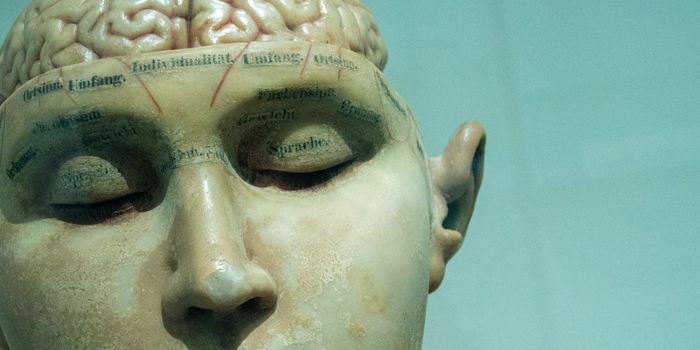

MAR 10, 2016InfographicsChildhood schizophrenia is a severe brain disorder which causes children to interpret reality abnormally. This type of m ...

APR 11, 2020NeuroscienceA study from China has found that stroke, an altered sense of consciousness and other neurological issues are relatively ...

JUL 10, 2018NeuroscienceLoneliness might not seem like a medical problem, but it can impact overall health, as well as brain health. Stress from ...

DEC 21, 2017NeuroscienceMental illness is sometimes looked at as a character weakness or something a person just has to "shake off." N ...

MAY 21, 2015NeuroscienceWe are in some ways in the infancy of understanding the impact on the brain of prolonged exposure to video game playing. ...

AUG 05, 2019Health & MedicineThe human brain is the most complex and least-understood part of the our body. With 86 billion brain cells and as many a ...